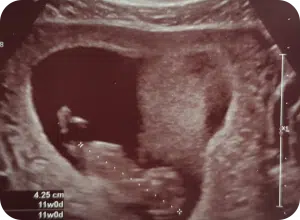

Na de eerste echo besefte ik me pas écht dat ik zwanger ben en waar ik het allemaal voor heb gedaan en nog steeds doe: er zit een kindje met een kloppend hartje in mijn buik. Vanaf de zwangerschapstest voelde ik al de enorme verantwoordelijkheid voor die kleine doperwt in mijn buik. Dit werd nog versterkt door het zien van een bewegend kindje op de echo. Ik weet één ding zeker: ik ga er alles aan doen om dit kleintje gezond ter wereld te laten komen.

De suikerachtbanen baren me zorgen deze maanden. Als ik me er al niet lekker door voel, hoe moet ons kleintje zich dan voelen? Gelukkig zijn alle echo’s steeds goed en vanaf week 12 neemt mijn misselijkheid af. Ik krijg weer wat meer energie en het allerbelangrijkste: de vlakke glucosegrafieken komen langzaam terug! Aan het eind van het eerste trimester wordt mijn HbA1c gecontroleerd en deze is prachtig: 33. Het harde werken wordt beloond.